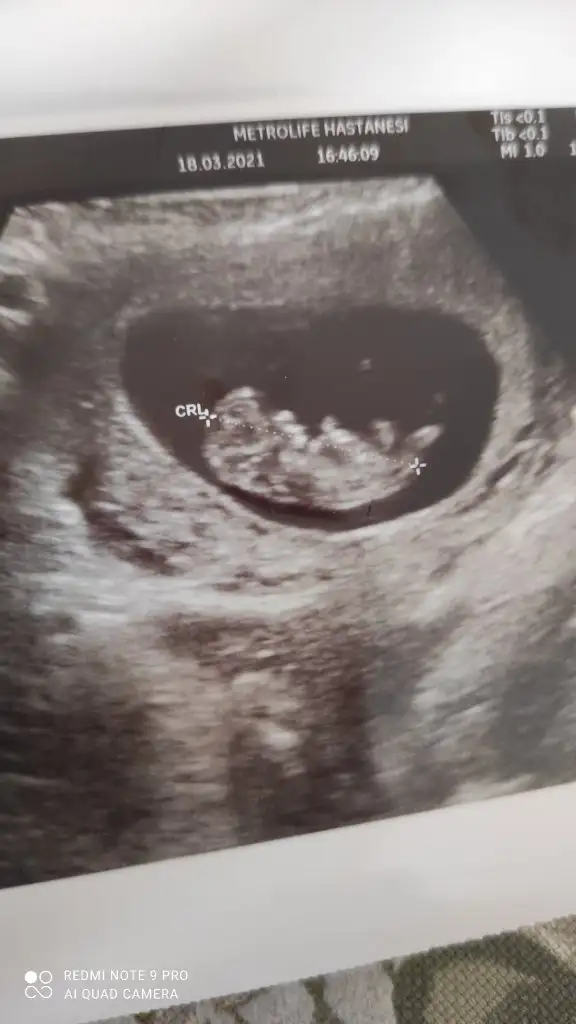

Kızlar 11+5 haftalık cinsiyet tahmini yapabilen var mı 🤩🙏🏻

• IMG_20210318_162633.webp

IMG_20210318_162633.webp

50,6 KB · Görüntüleme: 110